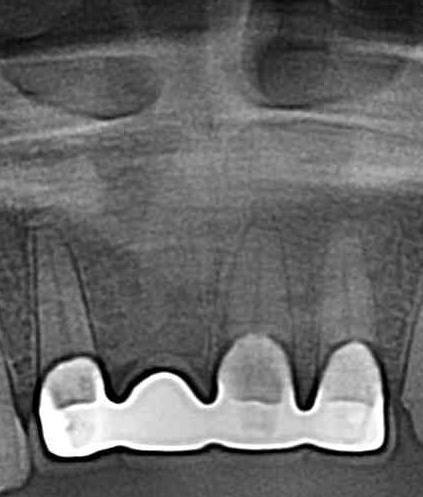

症例260歳 男性 主訴 前歯部がグラグラする

治療前

治療後(3年経過)

※説明

主訴 前歯部ブリッジの動揺を訴え来院。入れ歯の選択肢はなく、力学的に強く、両隣接歯を守るインプラントを選択。先ず過剰歯を抜歯。その後、2本インプラントを埋入し、同時に即時荷重非接触型の仮歯を装着。約3ヶ月間の免荷期間を経て、ジルコニアを装着。

リスクとしては、外科的侵襲がある。デメリットは、保険外診療の為、経済的負担がある。

費用 90万(税込) (オペ・仮歯・最終補綴物まで含む)